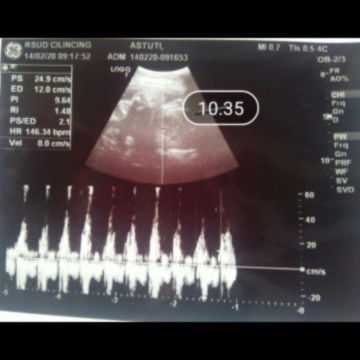

usg

usg 2d